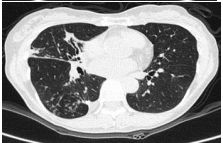

9.CC: 咳嗽 4 周,有痰